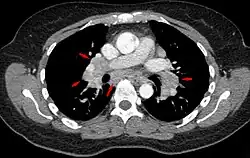

CT scan of the chest showing lymphadenopathy (arrows) in the mediastinum due to sarcoidosis

Diagnosis of sarcoidosis is a matter of exclusion, as there is no specific test for the condition. To exclude sarcoidosis in a case presenting with pulmonary symptoms might involve a chest radiograph, CT scan of chest, PET scan, CT-guided biopsy, mediastinoscopy, open lung biopsy, bronchoscopy with biopsy, endobronchial ultrasound, and endoscopic ultrasound with fine-needle aspiration of mediastinal lymph nodes (EBUS FNA). Tissue from biopsy of lymph nodes is subjected to both flow cytometry to rule out cancer and special stains (acid fast bacilli stain and Gömöri methenamine silver stain) to rule out microorganisms and fungi.[91][92][12][93]